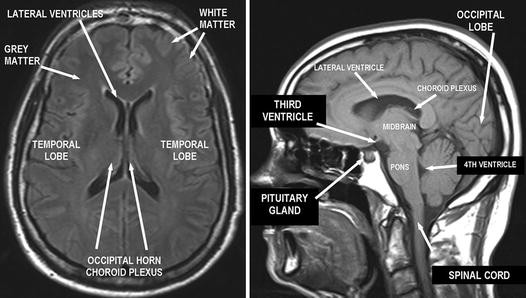

CNS Anatomy | SpringerLink